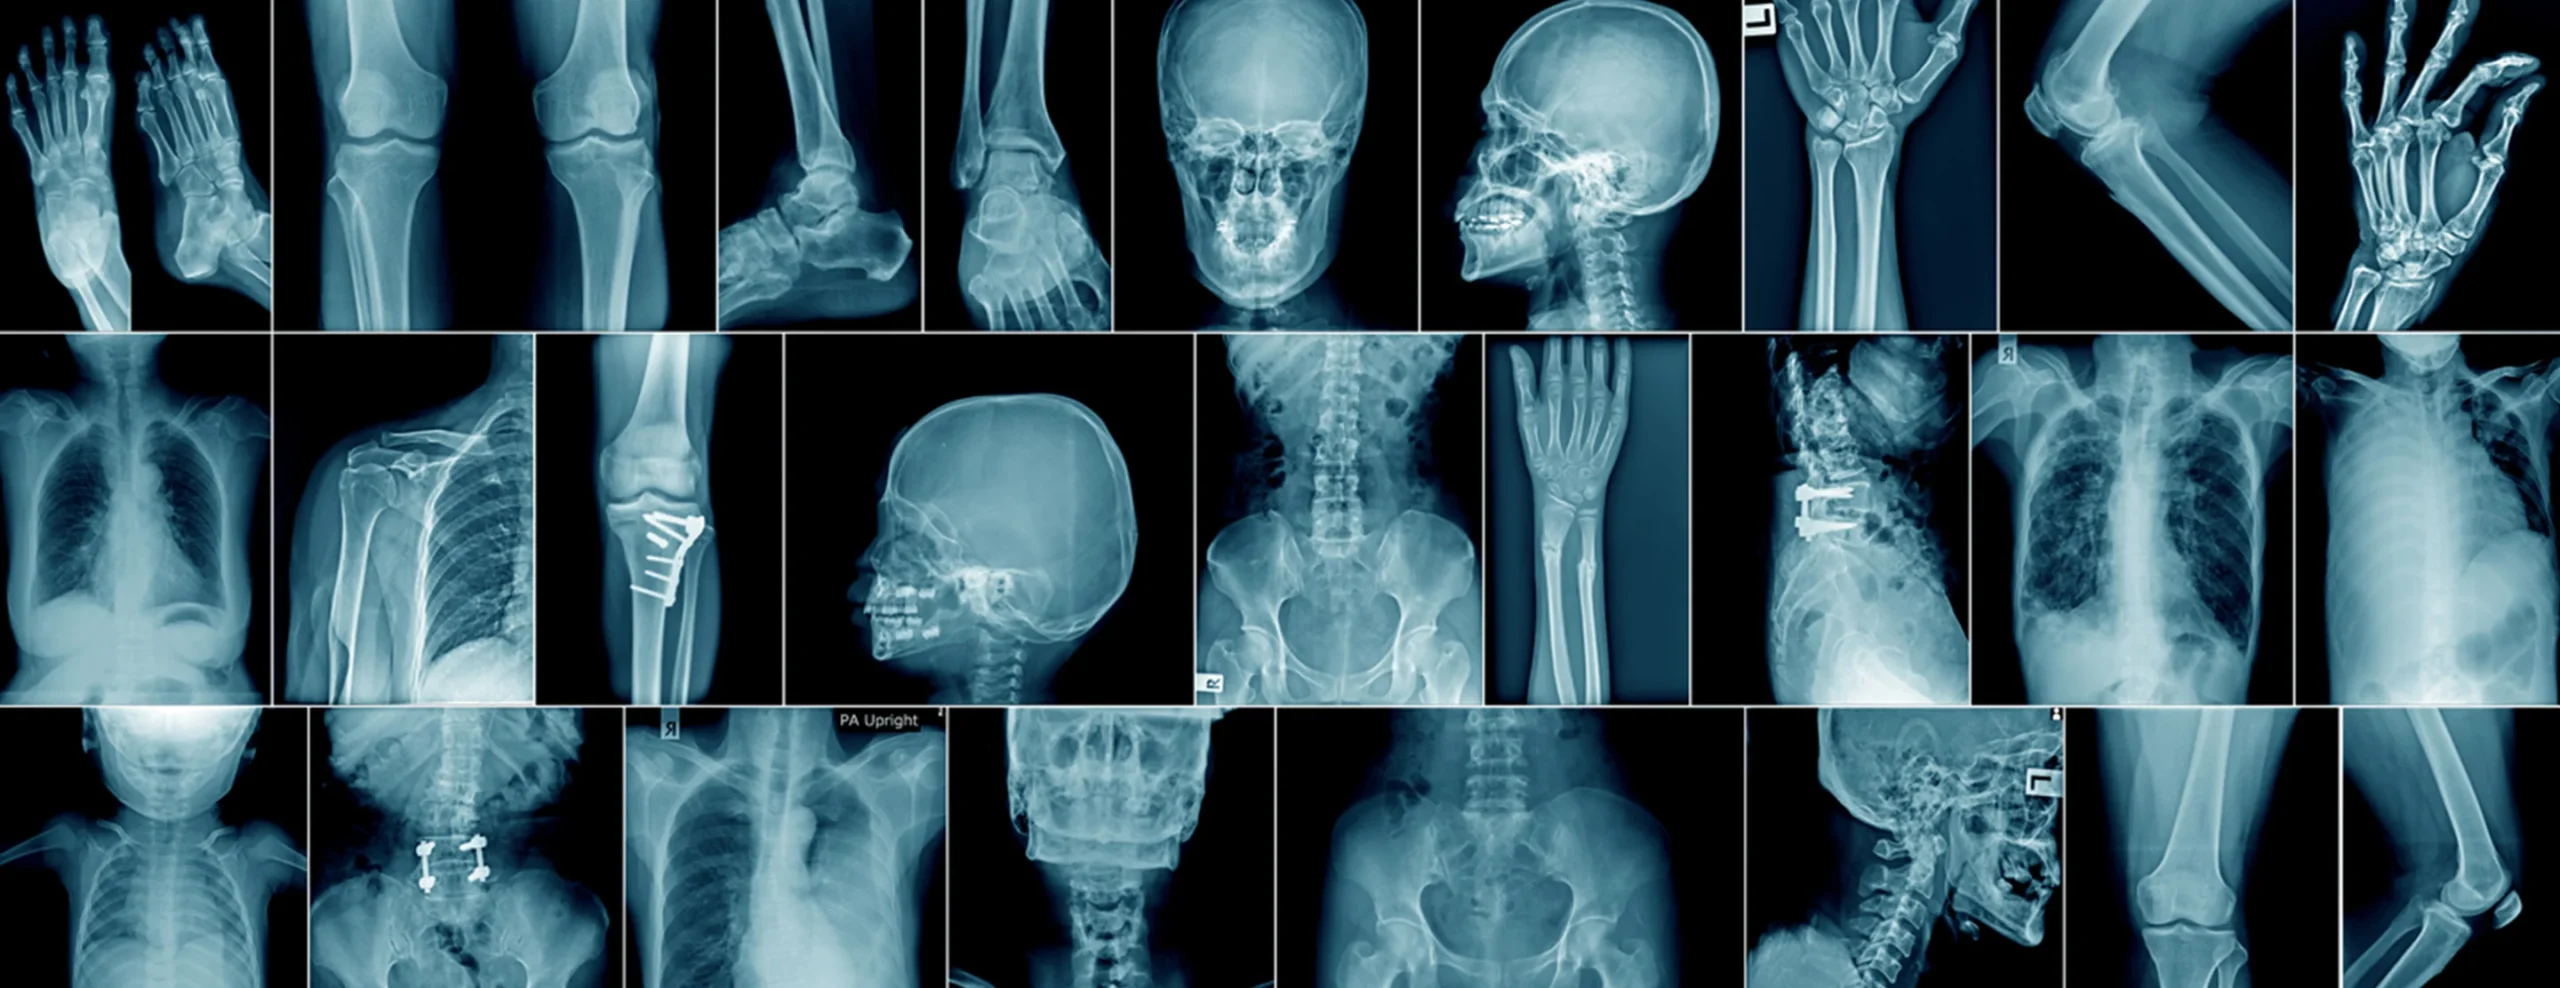

Perkhidmatan X-Ray Digital

Perkhidmatan X-ray digital kami menawarkan pengimejan berkualiti tinggi dengan pendedahan radiasi yang minimum, memastikan ketepatan serta keselamatan pesakit:

- Laporan X-Ray Digital – Laporan pantas, tepat dan mudah diakses oleh pesakit dan penyedia penjagaan kesihatan.